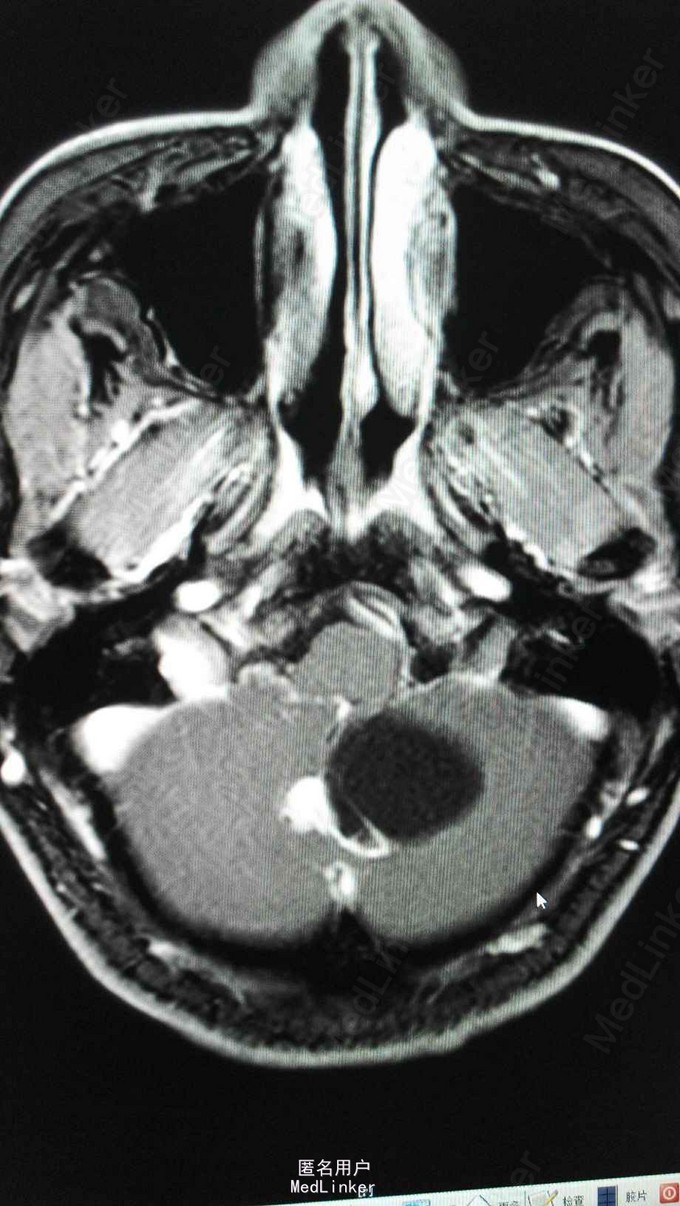

查体:T 36.5℃,P 81bpm,R 18bpm,BP 127/79mmHg;心肺腹及神经查体未及明显异常。 检查:三大常规、生化、凝血、乙肝、丙肝、梅毒、HIV未见明显异常。 头颅MRA:小脑蚓部占位,血管母细胞溜可能性大;左椎动脉颅内段局部轻度狭窄;左侧大脑前动脉A1段稍细。 腹部超声:右肾混合性占位性病变(中下极见一个大小约90*65*83mm的混合回声团,边界尚清,内回声不均,可见密集分布的无回声囊,呈蜂窝状);右肾局限性积液;胰腺内异常回声(多个大小不等的无回声囊,大者约12*11mm,边界清);双侧卵巢小囊(27*25mm(右)、25*25mm(左));肝、胆、脾未见明显异常;左肾、膀胱未见明显异常;双侧输尿管未见明显扩张;子宫未见明显异常。腹部增强CT ,胰腺多发囊性病变,右肾巨大占位,考虑肾癌。

VHL综合征 目前暂予完善相关检查及对症处理。